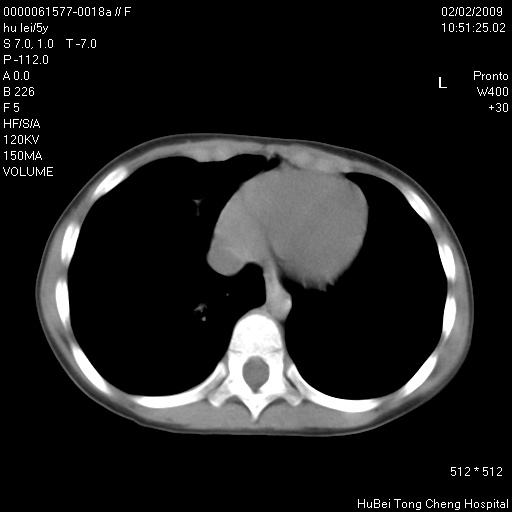

标题: PED1732:M5Y,右肺囊性占位!

患者:男,5。无明显不适,拍胸片考虑右肺囊肿。

行ct扫描,图象如下:

病灶与前胸壁和右上纵隔、叶间裂界限不清,病灶前缘及内侧缘看不到正常的肺组织,不能排除包裹性积液。